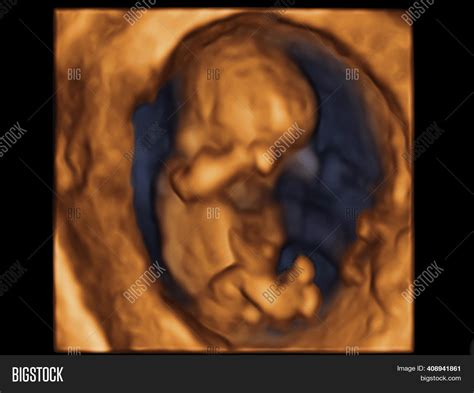

• Transabdominal or Transvaginal Ultrasound: At 10 weeks, a transabdominal ultrasound is usually sufficient. However, in some cases, a transvaginal ultrasound may be recommended for a clearer view.

• Fetal Measurements: The ultrasound technician will measure the fetus's crown-rump length (CRL) to assess growth and development.

• Organ Development: At this stage, the fetus's major organs, such as the heart, brain, and kidneys, are beginning to form.

• Fetal Heartbeat: The heartbeat is usually visible and can be heard using a Doppler device.

• Fetal Movement: Although it's too early for the mother to feel, the fetus may exhibit slight movements, such as curling and uncurling.